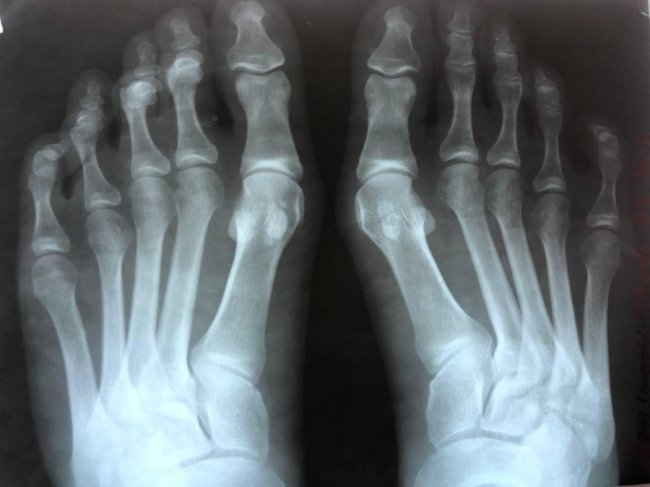

Волинські лікарі прооперували 24-річну пацієнтку, яка відчувала дискомфорт при ходьбі через викривлення перших пальців обох стоп.

Хворій під спинальною анестезією провели коригувальну операцію та реліз сухожилок першого пальця обох стоп.

Операція пройшла успішно. Пацієнтці дозволили вже з наступного дня навантажувати ногу.